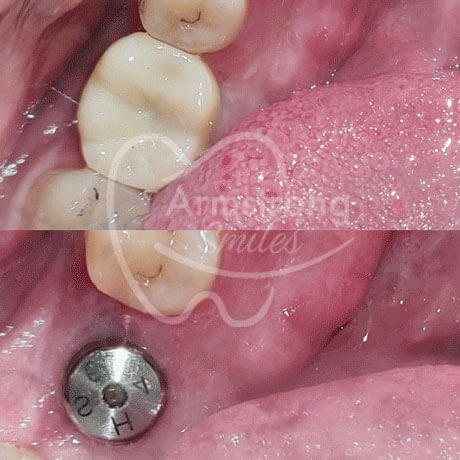

Dr Mina always takes the time to fully communicate with our patients, explaining all the various treatment options available to them. In addition to general dentistry, we offer cosmetic dentistry, including Invisalign clear aligners, veneers, crowns and more